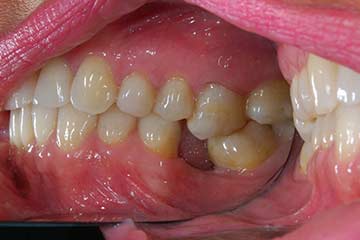

I denti irrecuperabili dell'arcata superiore ed inferiore del paziente di anni 65

sono stati sostituiti da 10 impianti, cioè protesi radicolari endo-ossee che sostengono le protesi fisse superiore ed inferiore.